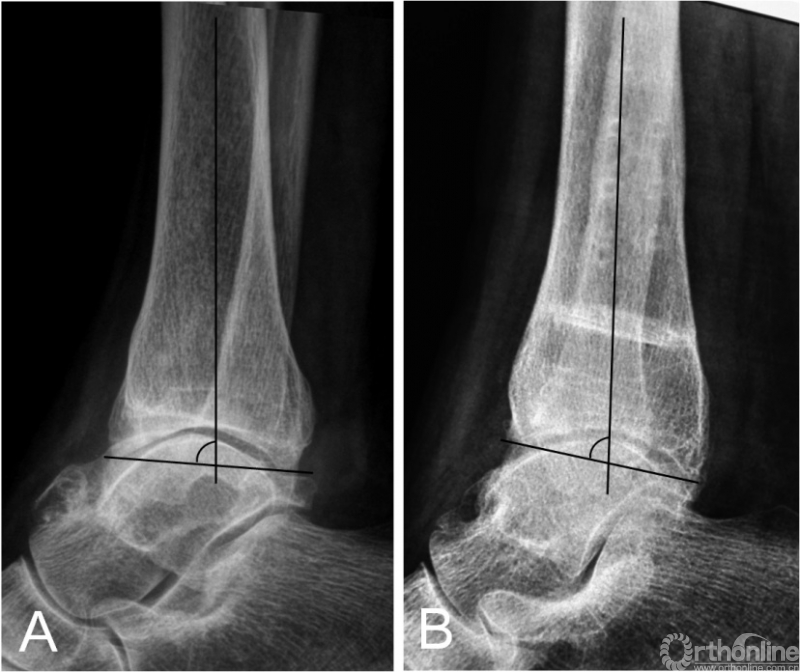

踝上截骨的主要目标之一就是矫正冠状面内翻畸形,即TAS角。临床研究指出,TAS的平均矫正程度从8.5~14.5°不等[6-21]。而对于踝关节OA患者矢状面TLS角为何会减小目前仍无定论[20,21]。本研究的TSA角在术前与术后未获得显著性差异,这可能与部分患者术前踝关节前侧存在显著骨赘有关(图4),因此术前的TLS测量常不能反映真实的TLS情况。因此,我们认为除非存在显著改变,术中无需刻意的去矫正TLS角。关于TT角在踝上截骨术中的意义目前争论最为激烈,研究报道间的差异性较大。一些作者指出,术后TT角得到显著矫正[8,11,13,16,17];然而,一些作者却强调踝上截骨并无矫正TT角的能力[6,12,14,21]。Tanaka等[21]报道的病例中,所有术前TT≥10°的患者,术后均未矫正至正常。Lee等[14]指出,术前TT角与术后TT角有相关性,他们认为在术前TT≥7.3°的患者,应放弃踝上截骨术。然而,在我们的患者中,67%(4/6)术前TT≥10°的患者,术后恢复到正常范围(TT≤4°[12])。Mann等[15]报道,在术后TT≥10°的患者,依然可以获得较好的临床功能。Kim等[11]则报道,没有任何影像学指标与术后功能有直接相关性。我们认为,在非终末期内翻型踝关节OA患者,通过踝上截骨来矫正负重力线及改善关节适配性是值得的,即使对于TT较大的患者。因为踝上截骨可以关节接触压强得到重新分布,外移踝关节机械轴[28],延缓甚至逆转OA的进程;甚至通过术后负重改变,使TT重新恢复至正常范围(图5)。我们认为,影像学的改变有时是需要时间的,正如OA的形成原因。Cheng等[7]报道,所有患者在随访时内侧间隙逐渐增宽,且常需要1年以上时间才能使踝关节间隙改善至理想程度。

图4 术前踝关节侧位X线片提示踝前骨赘形成,胫骨侧位关节面角为85°(4A);行关节清理及踝上截骨术后X线提示胫骨侧位关节面角为81°(4B)。

图5术前的距骨倾斜角(TT)为10.7°(5A),术后矫正至7.8°(5B);然而术后32个月随访时TT则已经恢复至1.5°(5C)。